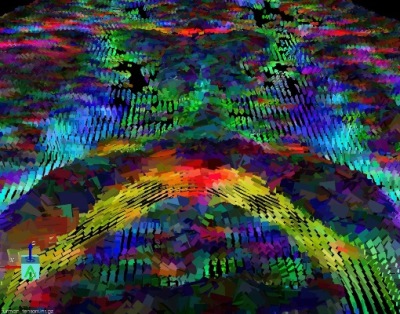

Diffusion Tensor Tractography MRI Image for Radiology

How it works: The white matter is the wiring of your brain. This wiring delivers the electrical signals from your cortex to your extremities. Diffusion Tensor imaging or DTI, uses the magnetic properties of water to create a map of the white matter in the brain. This data can be modeled into a 3 dimensional map of the white matter called tractography.

Equipment: Our MRI suite uses the latest Phillips 3.0 tesla magnet coupled with a state of the art post processing system. Our exams are personally tailored and monitored by a CAQ board certified neuroradiologist.

Benefits: DTI is used for presurgical and preradiation planning for an intracranial lesion that could potentially involve eloquent cerebral cortex. The DTI exam is tailored to the location of the lesion and the normal brain adjacent to it. The goal is to allow the neurosurgeon to plan the optimal, least invasive approach to a mass, and to allow the surgeon to more completely excise a mass while preserving as much normal function as possible. DTI also allows a patient to better understand the potential risks of having surgery. Our neurosurgical colleagues at OHSU can integrate the Tractography information into the operating suite using a 3D stereotactic software so the surgeons can see the location of the white matter tracts during the surgery. Many studies have shown improved morbidity and increased survival rates in patients who have had preoperative DTI.

Exam Preparation: The technologist will interview you prior to scan to make sure you have no contraindications to being in the MRI scanner. Patients with braces or other metal near the head or neck may not be suitable for DTI because of the artifacts the metal can cause. The exam is usually done in conjunction with a functional MRI (FMRI).

What to expect: DTI alone takes approximately 6 minutes of scanner time. During this time it is very important to remain still. The post-processing of the data to generate the trachtography by the neuroradiologist can take up to 1 hour. The DTI is usually done along with an FMRI examination.